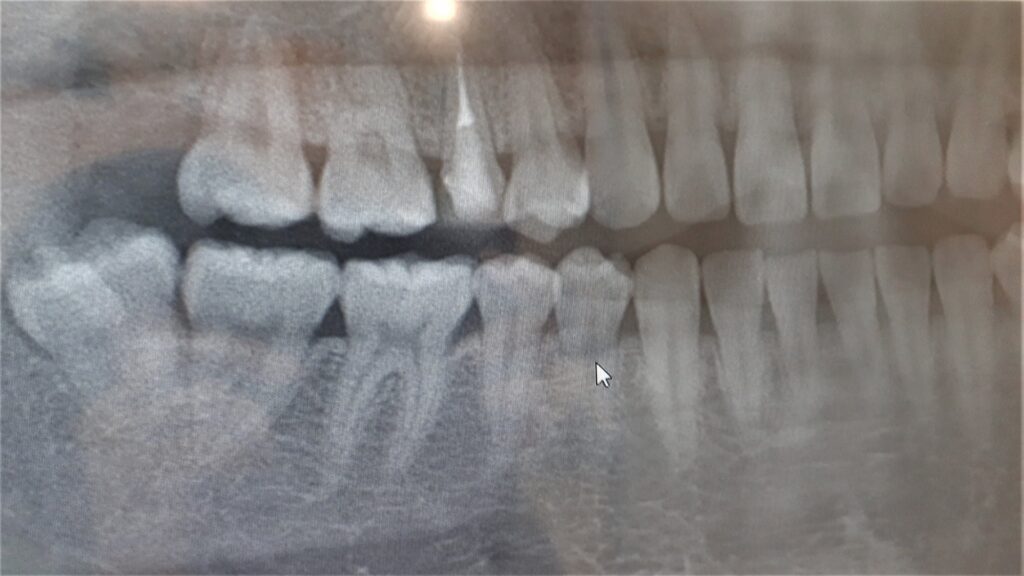

親知らずを抜歯すべきか?または抜かないか?これは患者さまからよく聞かれるお悩みの1つです。

親知らずは歯ブラシの届きにくい場所に生えていることが多く、虫歯や歯周病になりやすい、もしくはすでに罹患している可能性が高いため、抜歯をした方が良い場合があります。

親知らずは横や斜めに生えていたり埋まっていることがあり、隣の歯を押して歯並びを悪くさせる原因となる場合があります。気になるような感覚がある場合はご相談ください。

親知らずが横向きや斜めに生えていると歯並びに影響を与えます。それにより治療が長引いたり、矯正した歯並びが悪化する場合もあります。状況に応じて適切な対応をご提案します。

親知らずがまっすぐ生えており他の歯にも影響がないと判断される時は抜歯を行わない場合もあります。

2.完全に埋まっている

親知らずが完全に埋まっていて他の歯に悪影響がない場合はあえて抜歯しないこともあります。